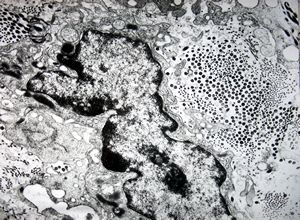

M, 62y. | mitosis … angiomatous tumor, v.s. Kaposi sarcoma

M, 62y. | angiomatous tumor, v.s. Kaposi sarcoma